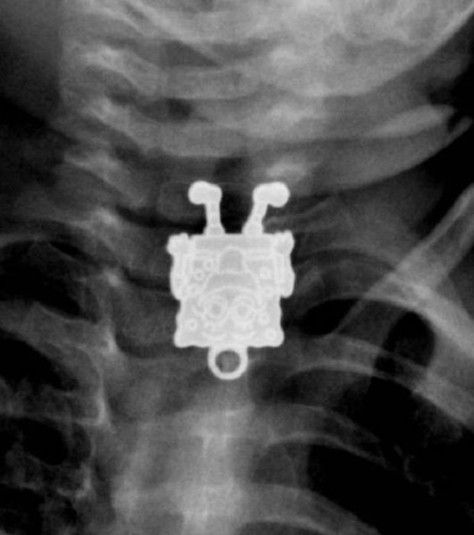

Предметы, которые не очень хочется видеть внутри себя

Под рентгеновскими лучами порой видны не только внутренние органы и кости, но и инородные тела, попавшие в организм

Истории попадания этих предметов в организм могут быть самыми невероятными и запутанными, но больше всего медиков интересует процесс их извлечения, впрочем, в этом заинтересованы и сами пациенты, допустившие нечто подобное со своим телом.